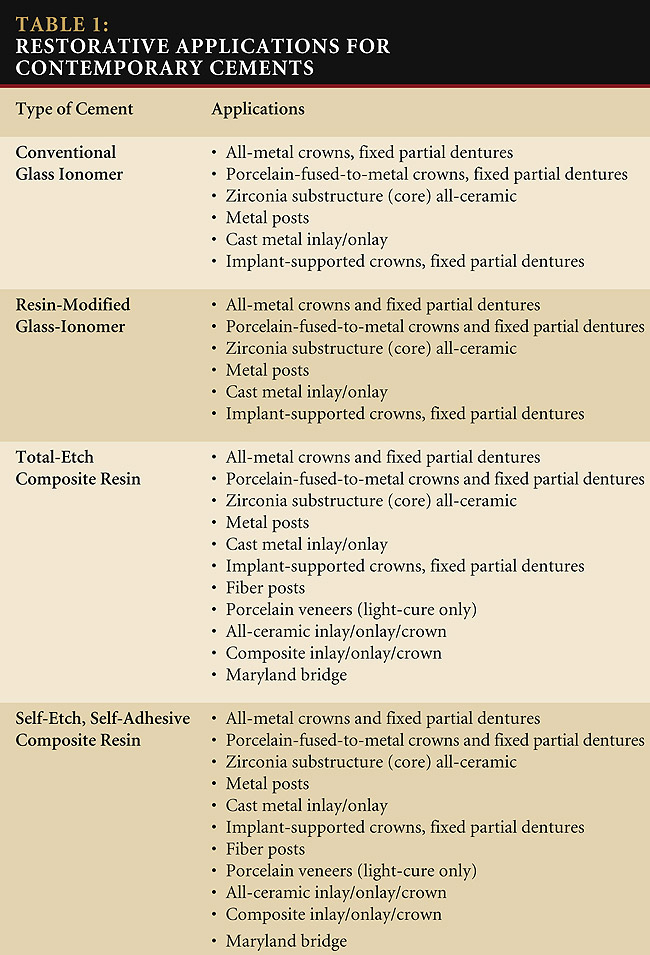

/trab03122/tab01t03122.jpg)